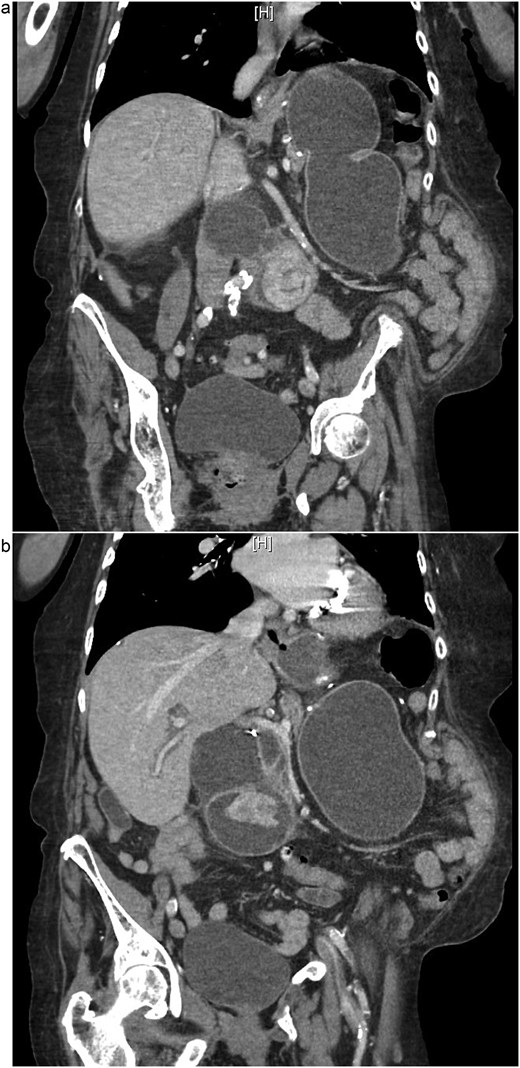

On examination, she was afebrile and hemodynamically stable. Her abdomen was mildly distended with epigastric tenderness and firmness. Laboratory workup revealed moderate leukocytosis (13.3 × 109/l), elevated lipase (288 U/l), and normal total bilirubin (0.8 mg/dl). Contrast-enhanced computed tomography (CT) demonstrated distention of the remnant stomach, duodenum (biliopancreatic limb), CBD, and intrahepatic ducts. A 9.0 × 3.4 cm heterogeneous mass was visualized in the duodenum, consistent with an obstructing gallstone (Figs 1–3).

(a and b) CT demonstrating gallstone in D3-D4 with BPD limb obstruction.